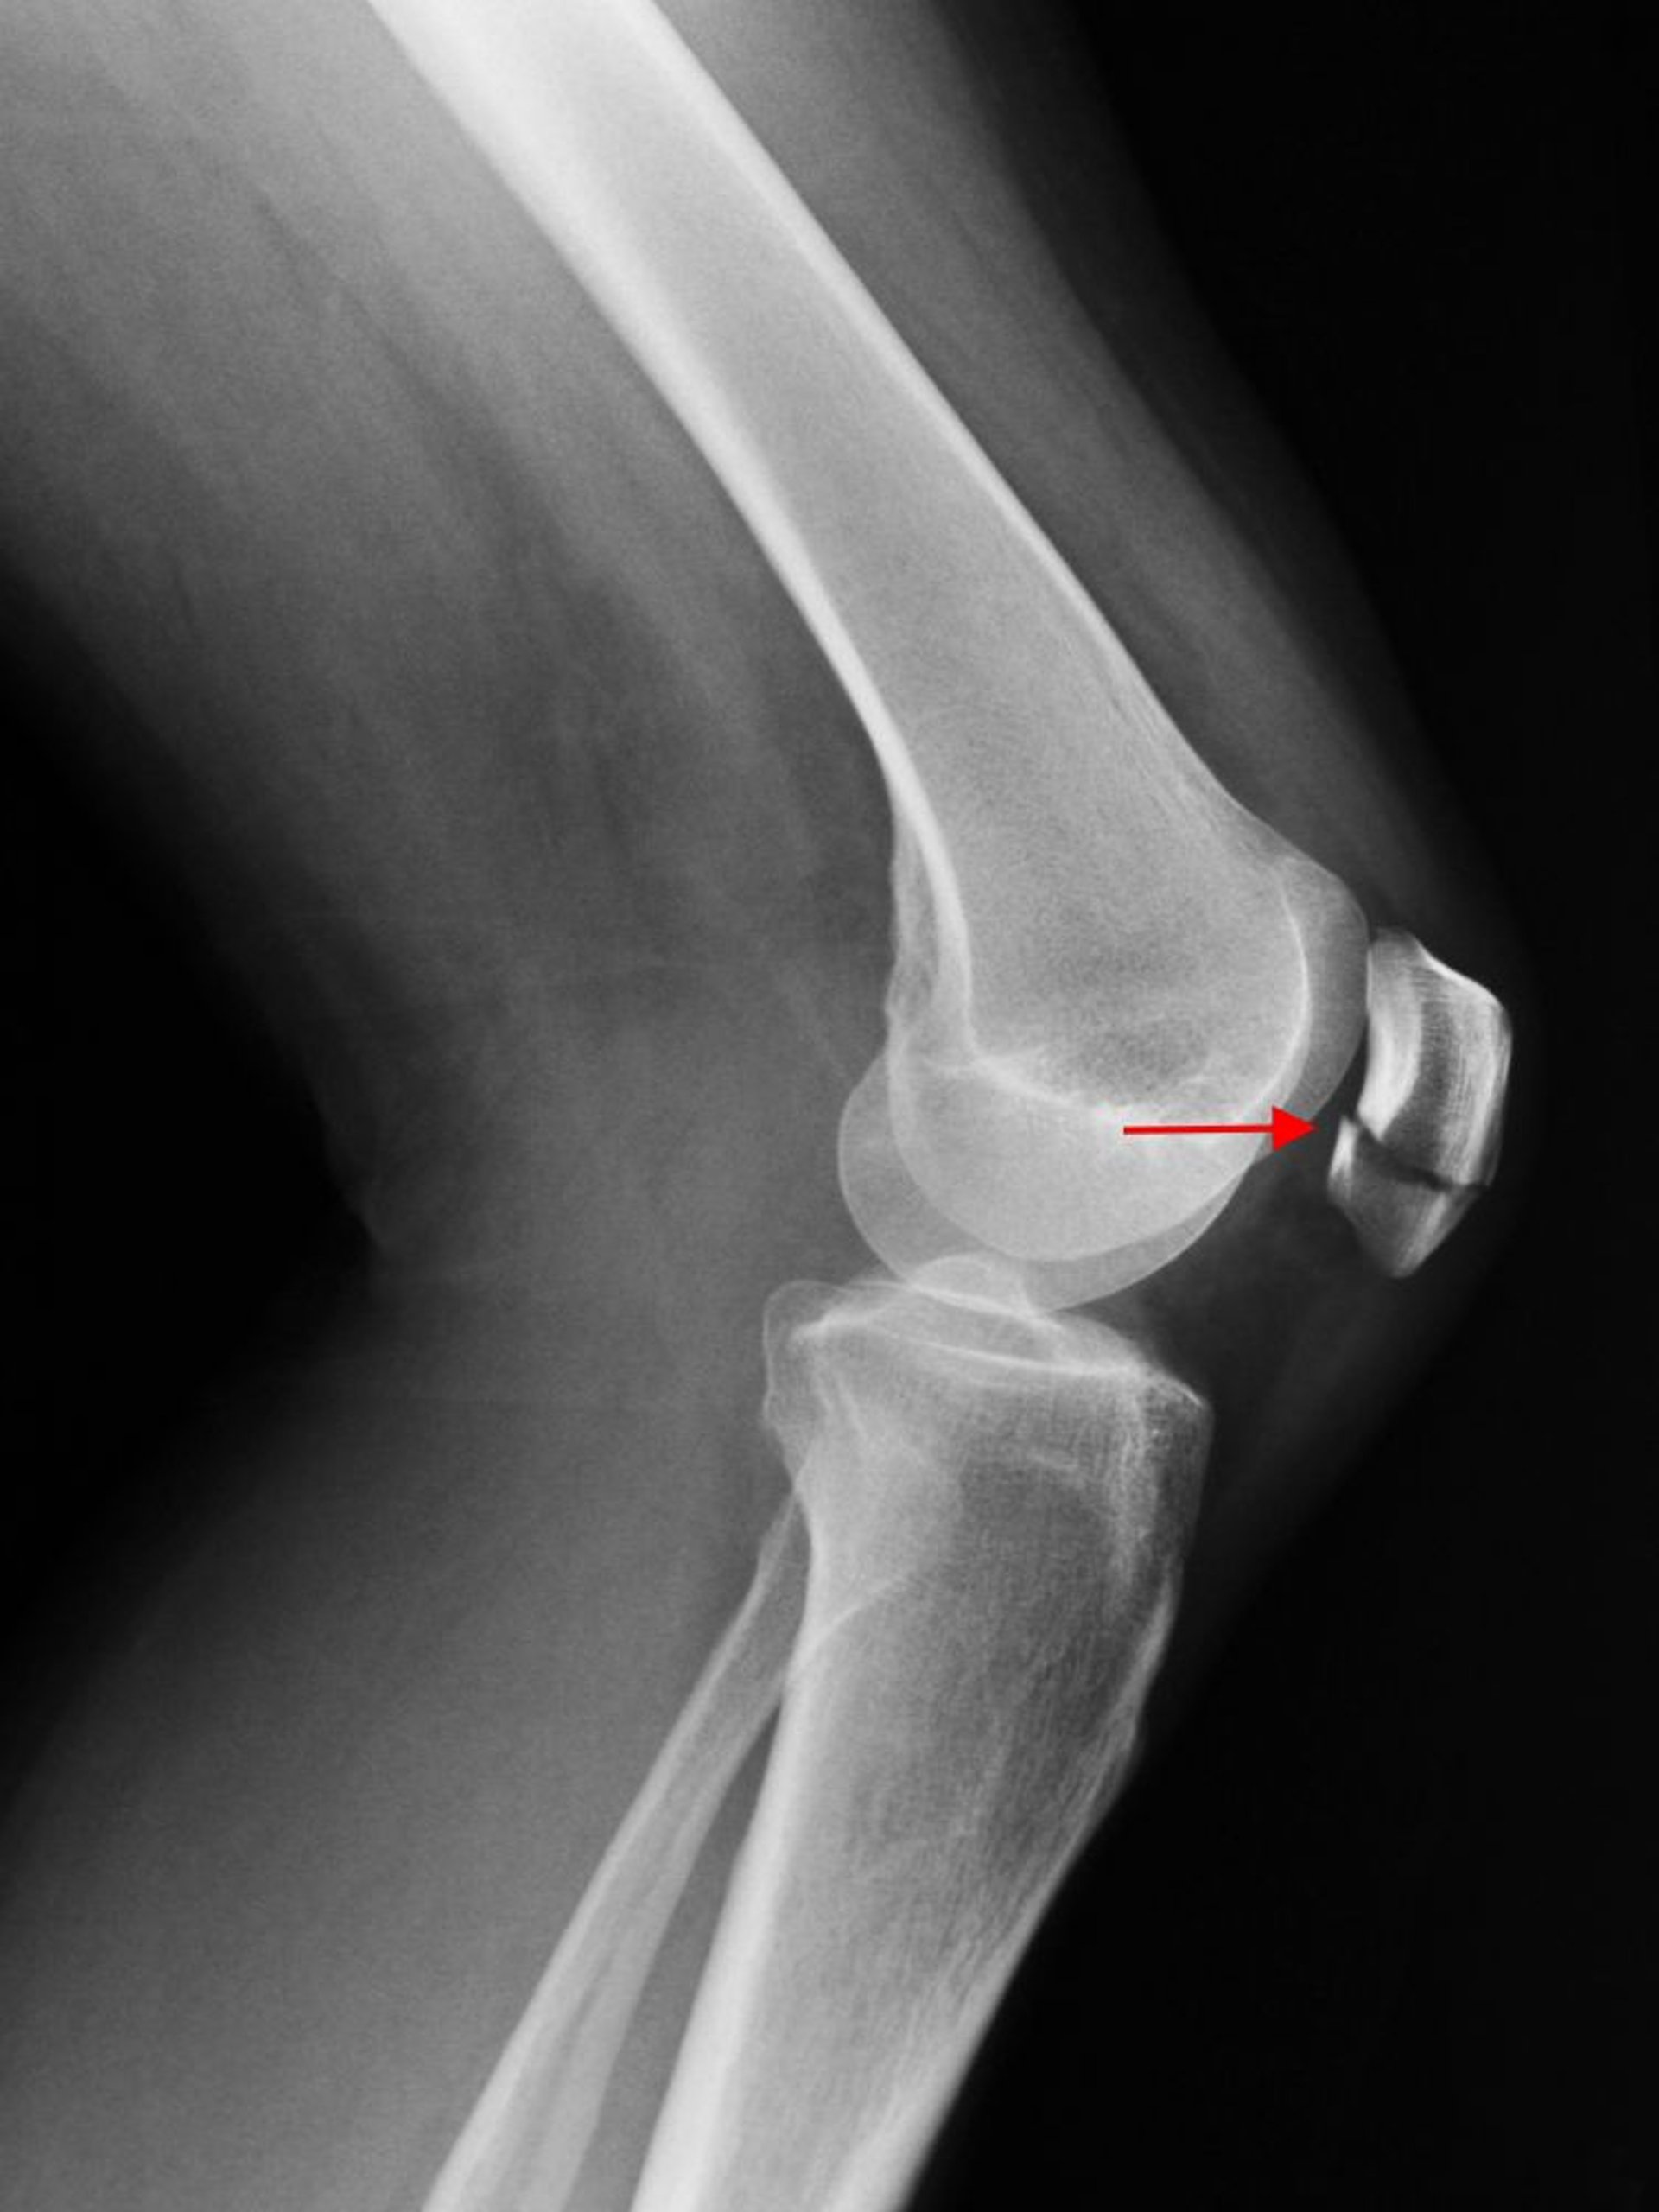

Frattura della rotula

Una radiografia di profilo del ginocchio mostra una frattura trasversale della rotula (freccia).